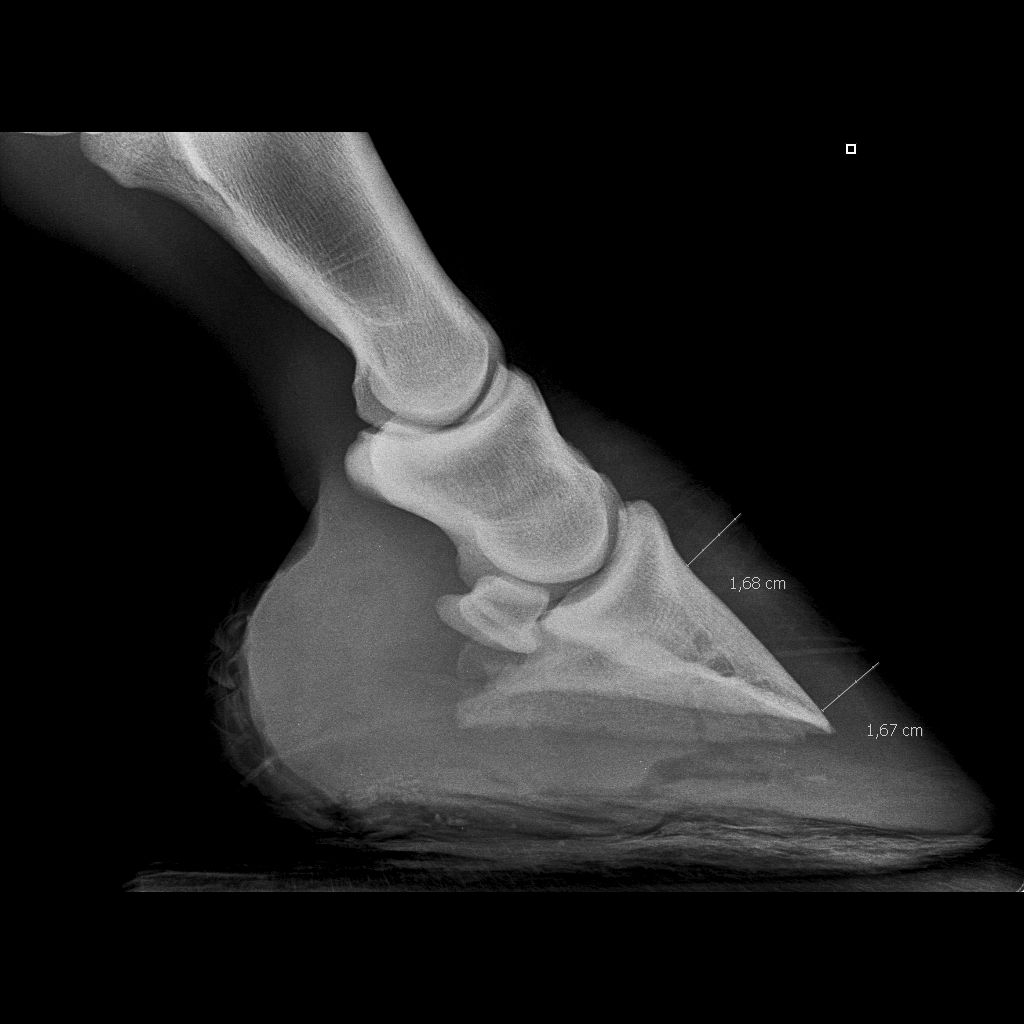

| Dire merci | quelqu'un pourrait-il m'aider à bien comprendre ce que l'on voit sur les radios des pieds de Ten. Le véto m'avait dit que l'abcès était prêt de l'os, avant, quand il est venu, il avait creusé en pointe de fourchette, or, Ten souffre toujours... demain, le maréchal vient pour lui coller des fers pour la soulager mais j'avais l'impression en regardant ses pieds que l'abcès allait percer en glôme....alors je voulais savoir si au vu des radios on pouvait savoir si l'abcès était vraiment localisé où le véto avait creusé....parceque sinon, demain matin, j'aurais dit au maréchal d'essayer de "fouiller" ailleurs.... donc sur les radios : ![]() ![]() Les abcès sont-ils bien les sortes de cavités noires juste en dessous l'os ? (de part et d'autre du "1" sur une des radios) |

| Dire merci | c'est pas évident de voir les abcès à la radio, c'est de meme densité que les tissus, on voit surtout là ou le véto a creusé. Cependant il y a des lacunes sur la 3eme phalange que je me garderais bien d'interpréter n'étant pas véto mais qui ne me semblent pas normales, faudrait demander à El Bimbo |

| Dire merci | nan nan suis pas véto....et je me posais la même question que Filou : c'est quoi ce trou noir dans P3 ? une vascularisation ? j'avais jamais vu non plus....![]() Tu peux nous photographier le pied pour nous montrer pourquoi tu penses que l'abcès percera au niveau des glômes ? ![]() |

| Dire merci | Je sais pas si ça peut aider, mais j'ai eu une experience similaire en septembre dernier : J'ai eu un problème de boiterie prolongée suite à un clou de rue, mais ne sachant pas alors si ça avait fait un abcès je lai emmené à Grosbois voir un spécialiste. D'après la radio il voyait l'abcès mais il ma dit que c'etait difficile à lire sur une radio.Ce n'est pas le trou en pointe de fourchette, ça c'est la sole qui a été grattée par le 1er véto (qui n'avait rien trouvé) ![]() Là on voit 2 mois après la cicatrice une fois l'abcès percé et soigné à Grosbois: Enfn tout ça pour dire que sans etre un très bon spécialiste, c'est hasardeux de vouloir interpréter une radio. PS : le trou dans P3, c'est normal il y a des vaisseaux sanguins (j'ai demandé la même chose là bas !) |

| Dire merci | Il s'est percé la sole début aout, et je l'ai emmené à Grosbois début septembre, donc 1 mois de boiterie avec des hauts et des bas, surtout que le premier véto avait donné des antibios, ce qui n'est pas bon du tout car l'abcès a été masqué et s'est "enkysté" pour mieux faire souffrir 3 semaines plus tard ![]() Heureusement, une fois percé, nettoyé et protégé, il remarchait normalement dès le premier jour ![]() Sur ma radio on peut voir la pointe du clou qui a touché l'os quand même. Tu n'a pas des photos du dessous pied pour comparer ce qui a été creusé ? Parce que sur ta radio on voit 2 fistules qui descendent perpendiculairement, c'est quoi ? |

| Dire merci | ![]() Les fistules dont je parle sont en jaune, le vert c'est je pense le trou creusé. Après je ne fait que des hypothèses d'amateur évidement ![]() |